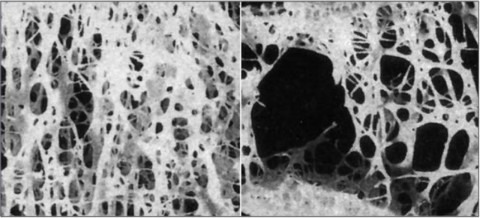

우리 뼈에는 조골세포와 파골세포가 있는데, 이 중에서 파골세포는 혈액의 칼슘이 부족하거나 오래된 뼈를 새 뼈로 교체할 때 뼈를 분해하는 세포이고, 조골세포는 반대로 뼈를 생성하고 재생하는 세포입니다. 이처럼 우리 뼈는 조골세포와 파골세포의 상호작용으로 유지되고 재생되고 있습니다.

골 형성과 골 흡수가 균형을 이루지 못할 경우에 발생하는 질환을 말하는데, 골량 감소와 미세구조 손상으로 인해 뼈가 약해져 부러지기 쉬운 상태가 되며 노년기에 많이 나타나는 질환입니다. 특히 낙상 위험이 커지는 겨울철에 골다공증이 있는 고령자는 골절 사고를 유의해야 합니다.